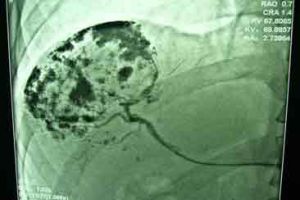

4.肝動脈造影:病變部位周邊出現“血管湖”影像,造影劑滯留時間較長。

(2)肝動脈造影及腫瘤動脈栓塞。